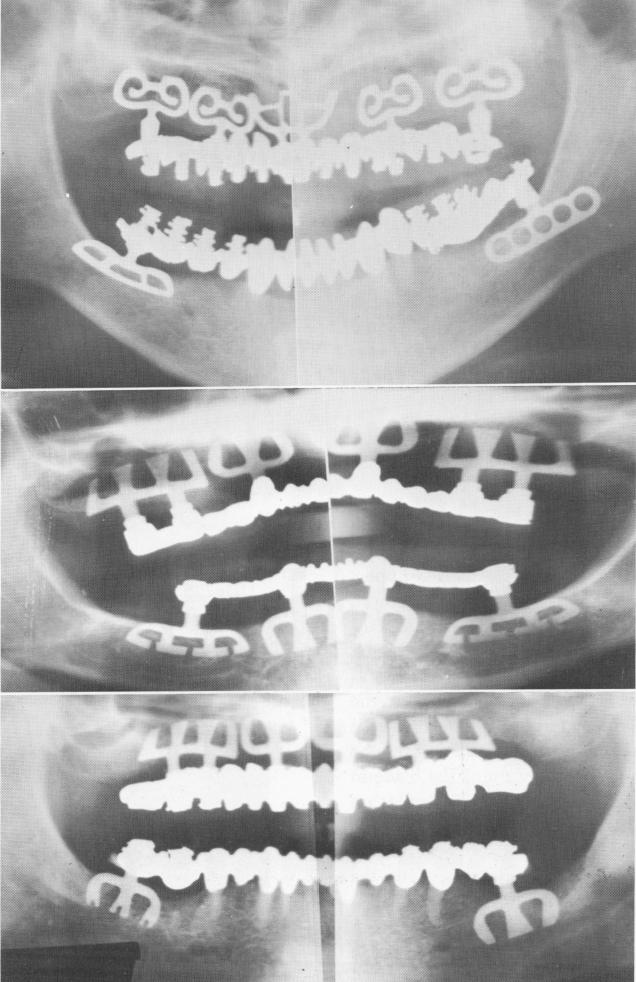

Blade implants were set into the bone in both right and left posterior quadrants of the mandible and into the completely edentulous maxilla (Fig. 11-160). Temporary acrylic splints were processed

for the patient to carry him over until all the tissue had healed.

When the tissues had healed (Fig. 11-161), all necessary impressions were taken for upper and lower full arch fixed dentures. These were made in acrylic over gold, because the materials are lighter

Fig. 11-165. A, A Panorex of the finished case. (From Linkow, L. I.: Status of oral implants, 1969, Inform. Odontostomat., Vol. 1, 1969.) B and C, Two other examples of completely edentulous maxillae restored with full arch fixed prostheses. In B both jaws were completely edentulous. They were restored with porcelain-baked-to-palladium-and-gold. In C they were made of acrylic processed to gold.

1 Panorex of finished maxillary and mandibular prosthesis in place